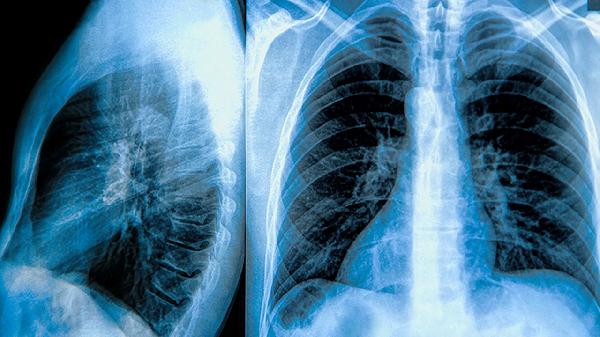

肺粟粒结节可能由肺结核、尘肺、真菌感染、转移性肿瘤等原因引起,可通过抗感染治疗、手术切除、化疗等方式干预。

发现肺粟粒结节应完善CT引导穿刺等检查明确性质,避免吸烟及接触污染空气,定期随访观察结节变化情况。